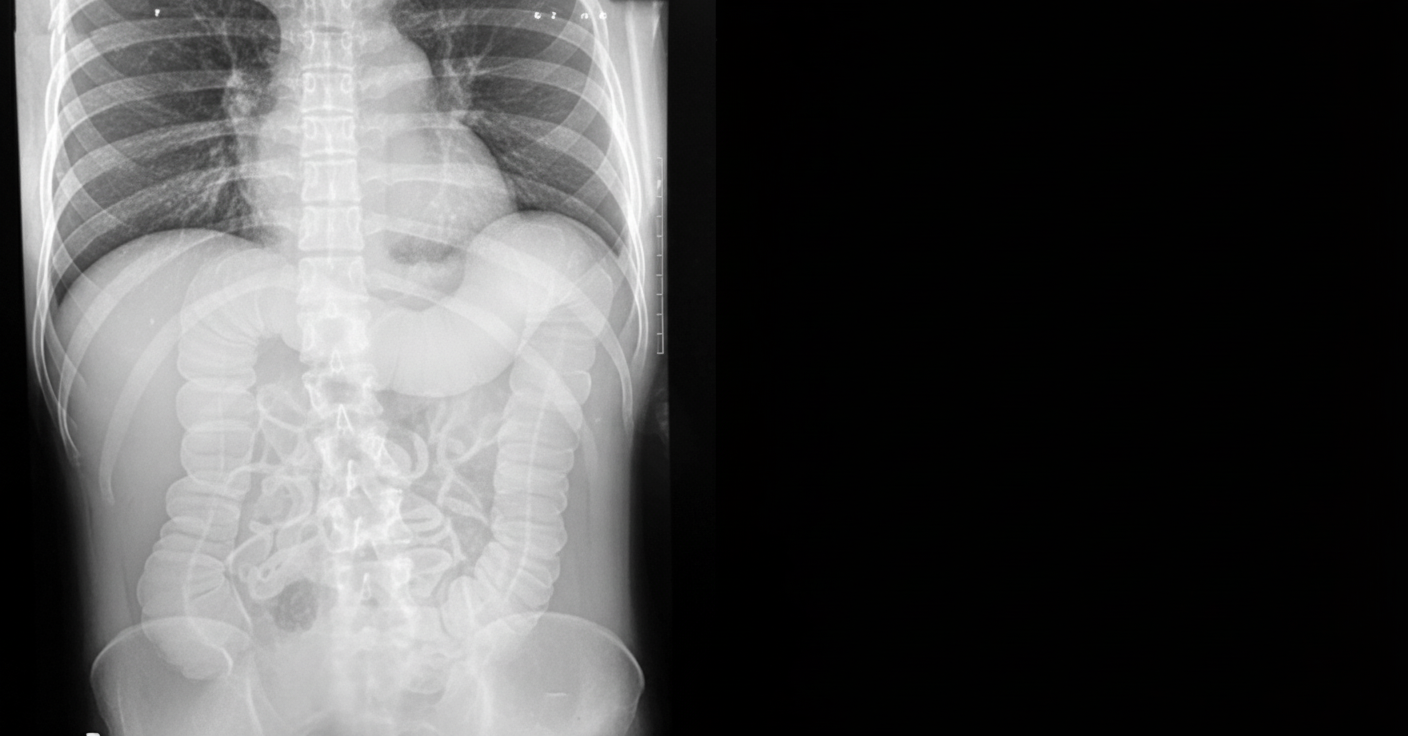

A patient with a known history of ulcerative colitis presents to the emergency department with abdominal distension and tenderness. An abdominal X-ray was performed. Which of the following is true regarding the patient's condition?

Explanation: ***Toxic megacolon*** - **Abdominal distension** and **tenderness** in a UC patient with **dilated transverse colon >6cm** and **loss of haustra** on X-ray are classic findings of **toxic megacolon**. - This is a **life-threatening complication** of ulcerative colitis requiring immediate medical intervention and possible surgical management. *Toxic megacolon is rarely seen in ulcerative colitis* - This statement is incorrect as **toxic megacolon** is a **well-recognized serious complication** of ulcerative colitis, occurring in 1-9% of patients. - It represents **acute colonic dilatation** with **systemic toxicity** and is considered a **medical emergency** in UC patients. *Sigmoid volvulus* - **Sigmoid volvulus** presents with a characteristic **coffee bean sign** on X-ray, showing twisted sigmoid colon with two air-fluid levels. - The clinical presentation typically involves **sudden onset crampy pain** and **obstipation**, different from the systemic toxicity seen in this UC patient. *Adhesions* - **Intestinal adhesions** cause **mechanical bowel obstruction** with **dilated small bowel loops** and **air-fluid levels** on X-ray. - The history lacks **previous abdominal surgery** or trauma, and adhesions don't typically cause **colonic dilatation** with **loss of haustra** as seen here.